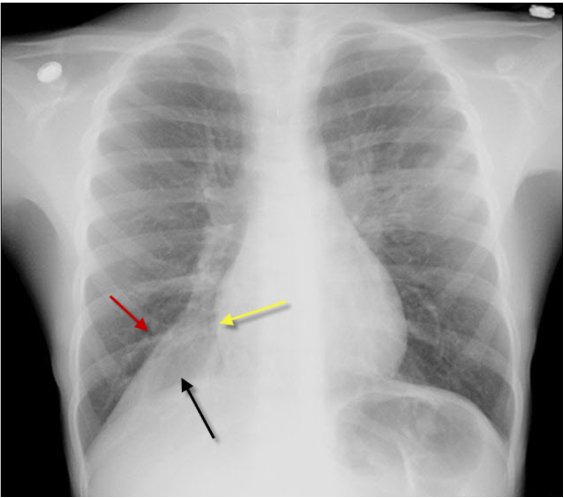

Lungestase/ødem:

Karakteristisk:

* Alveolært ødem

* Kerley B lines (septale linjer, horisontale, aldrig længere end 2 cm, ses bedst perifert i lungerne)

* Pleural effusion

* Kardiomegali

* Fremtrædende kar i overlapperne

A

Diagnose?

Hjertesvigt